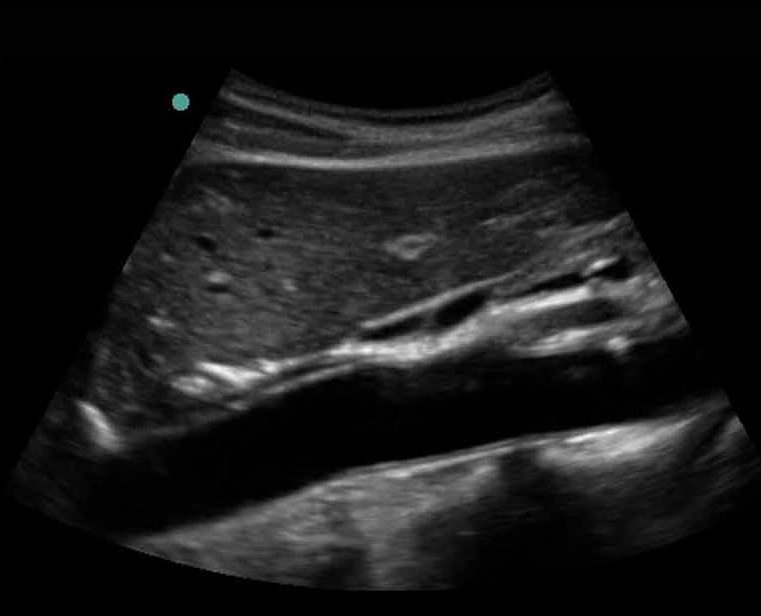

Bild: Aorta, proximal, longitudinal